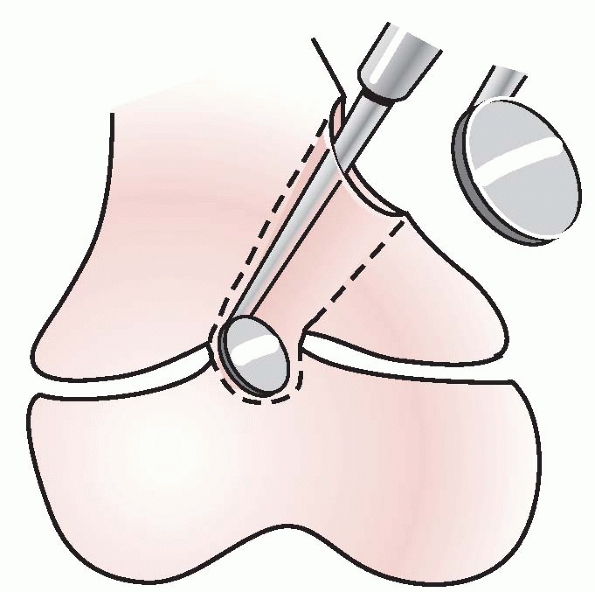

that minimizes trauma to the residual physis. Central lesions should be

approached through either a metaphyseal window (Fig. 5-41)

or through the intramedullary canal after a metaphyseal osteotomy.

Peripheral lesions are approached directly, resecting the overlying

periosteum to help prevent reformation of the arrest. Intraoperative

imaging (fluoroscopy) is needed to keep the surgeon oriented properly

to the arrest and the residual healthy physis. Care to provide adequate

visualization of the surgical cavity is essential, because

visualization is usually difficult even under “ideal” circumstances. A

brilliant light source, magnification, and a dry surgical field are

very helpful. An arthroscope can be inserted into a metaphyseal cavity

to permit a circumferential view of the resection area. A high-speed

burr worked in a gentle to-and-fro movement perpendicular to the physis

is usually the most effective way to gradually remove the bone

composing the arrest and expose the residual healthy physis (Fig. 5-42).

By the end of the resection, all of the bridging bone between the

metaphysis and epiphysis should be removed, leaving a void in the

physis where the arrest had been, and the perimeter of the healthy

residual physis should be visible circumferentially at the margins of

the surgically created cavity (Fig. 5-43).

| Figure 5-41 Central arrests are approached through a metaphyseal “window” or the medullary canal after metaphyseal osteotomy. |

| Figure 5-42 The arrest is removed, leaving in its place a metaphyseal-epiphyseal cavity with intact physis surrounding the area of resection. |